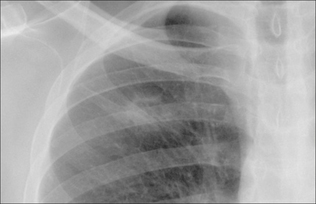

image

Figure 20.1 A SPN is a common finding on adult CXRs. Approximately 60–70% are benign. Some 30–40% are malignant2-4.